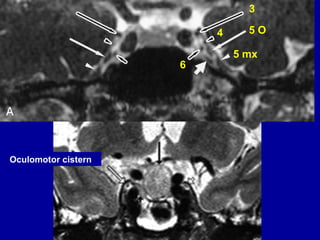

Cavernous segment

• The oculomotor nerve enters the cavernous

sinus superior to the petro-clinoid ligament and

inferior to the inter-clinoid ligament.

• The cavernous segment of the oculomotor

nerve course through the lateral wall of the

cavernous sinus superiorly.

• It is surrounded by CSF dural cuff (oculomotor

cistern).

4 5 O

6

3

5 mx

Oculomotor cistern